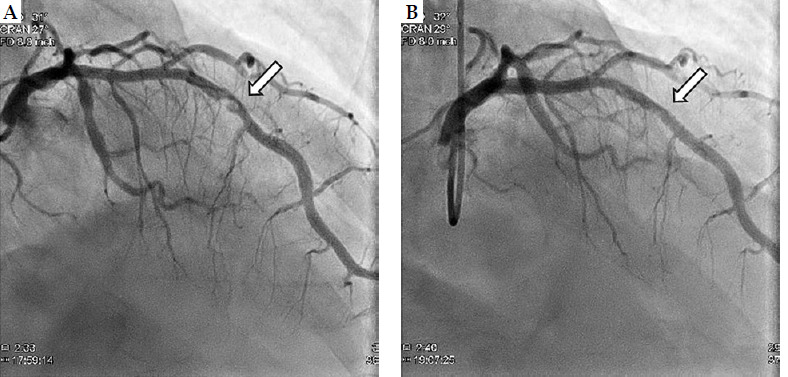

在近距离治疗期间和之后发生的主要全身并发症是罕见的。在此,我们描述了一例因低剂量率近距离放射治疗后因库尼斯综合征引起的急性心肌梗死,患者为70岁男性,对香蕉过敏。全麻下低剂量近距离放疗后,患者主诉全身瘙痒;心电图示心室颤动。心导管检查显示左侧前降支狭窄99%;因此,立即进行了经皮冠状动脉介入治疗。在这种情况下,被认为是库尼斯综合征,这是由于在经直肠超声检查中使用避孕套时对乳胶过敏引起的。

Major systemic complications during and immediately after brachytherapy are rare. Herein, we described a case of acute myocardial infarction due to Kounis syndrome after low-dose-rate brachytherapy in a 70-year-old man with a banana allergy. Following low-dose-rate brachytherapy under general anesthesia, the patient complained of itching throughout his body; electrocardiography showed ventricular fibrillation. Cardiac catheterization revealed 99% stenosis in the left anterior descending artery; consequently, percutaneous coronary intervention was performed promptly. In this case, Kounis syndrome was considered, which was caused by latex allergy to condoms used during trans-rectal ultrasound examinations.